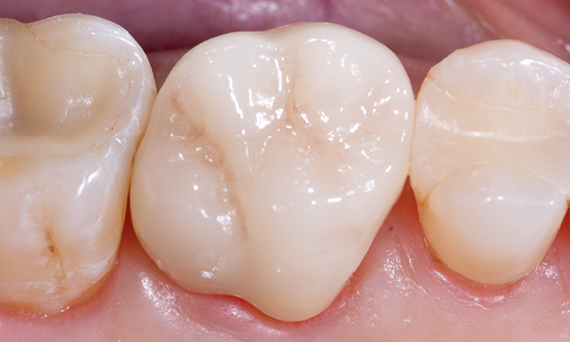

Before: Fractured ceramic restoration made from a leucite-reinforced glass-ceramic after a clinical service time of 12 years.

After: Chairside-fabricated restoration made from an advanced lithium-disilicate ceramic CEREC Tessera.